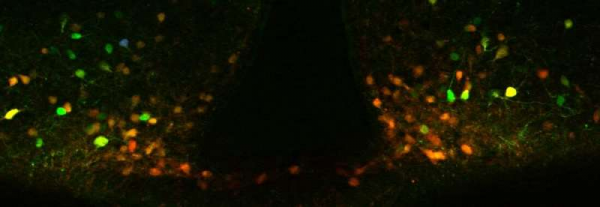

![]()

Williams博士實驗室的顯微鏡影象描繪了下丘腦弓形核:綠色的細胞是POMC神經元,紅色的細胞是表達瘦素受體的神經元,黃色的細胞是表達瘦素受體的POMC神經元